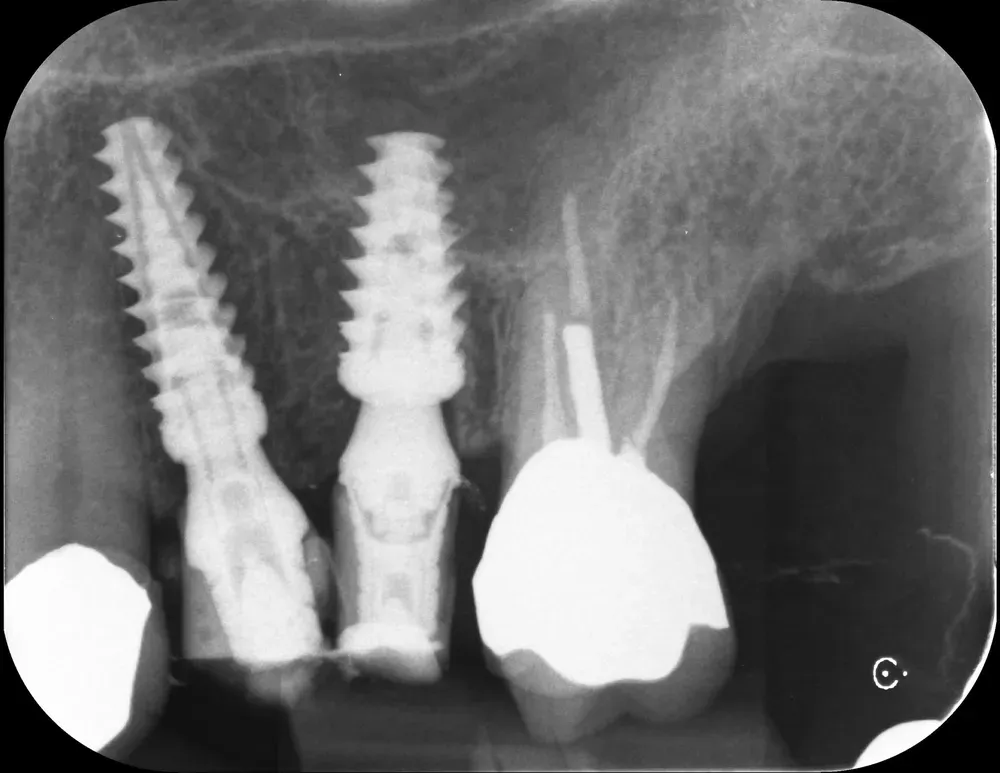

Di seguito, le radiografie periapicali mostrano gli impianti appena inseriti e gli abutment con i provvisori.

Rx Periapicale Post-op

Rx Periapicale con abutment e provvisori